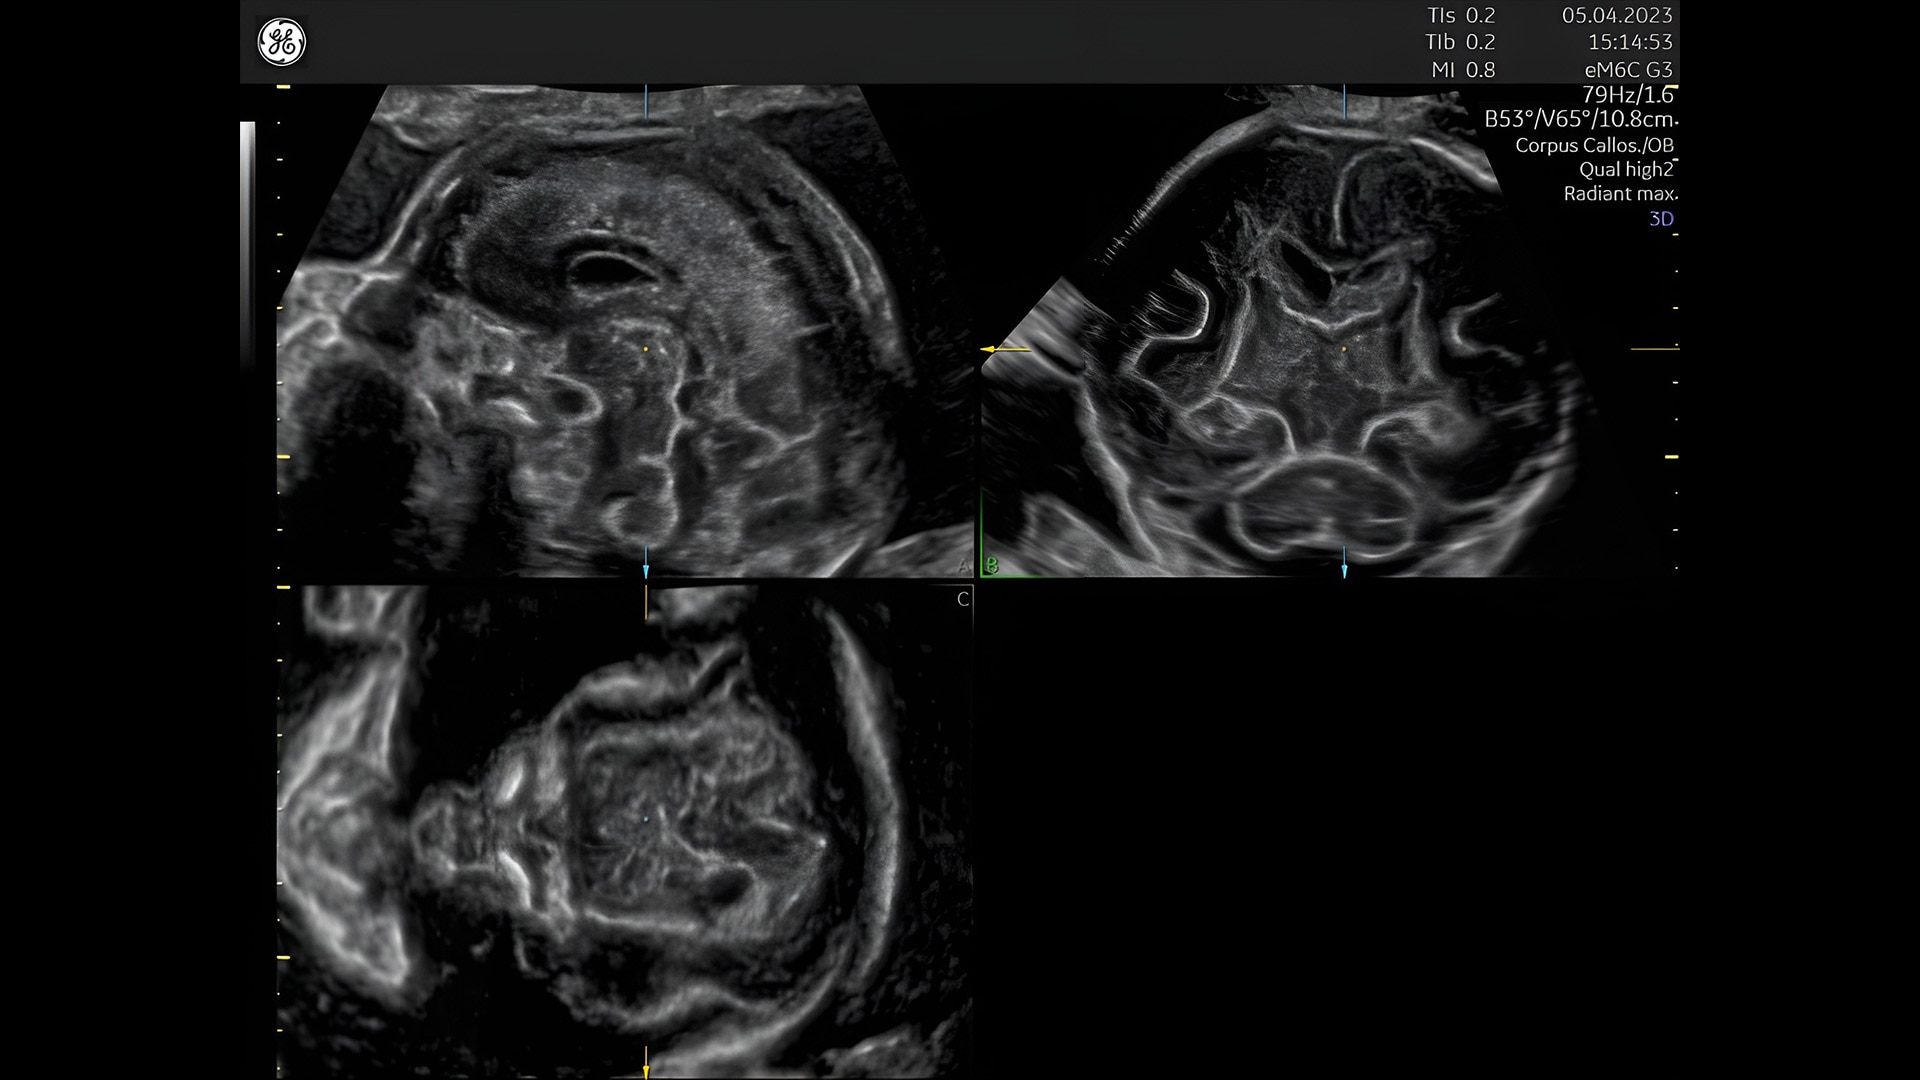

First trimester exams

Perform detailed exams with high-resolution for early insights to fetal health